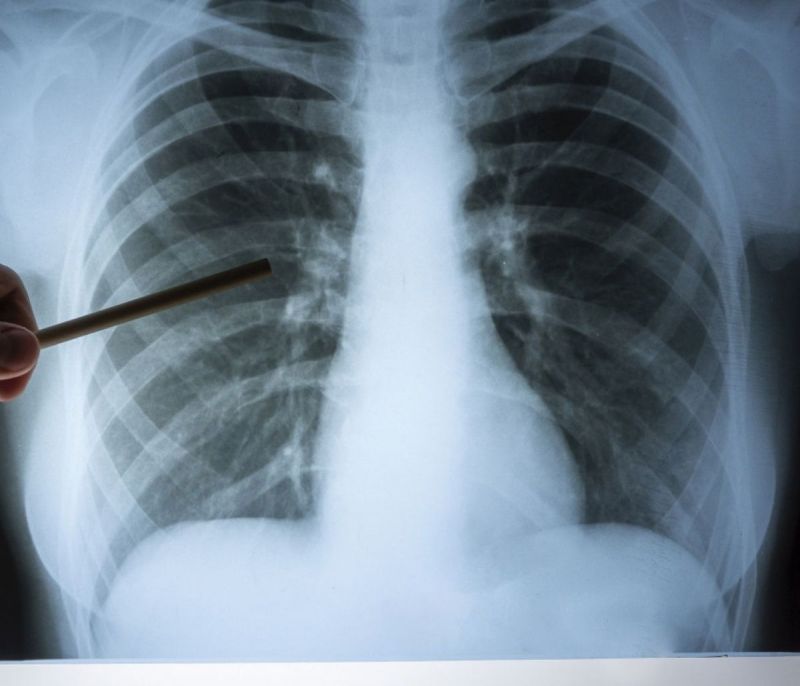

Η κυστική ίνωση είναι η πιο συχνή κληρονομική νόσος της λευκής φυλής.

Υπολογίζεται ότι προσβάλλει περίπου 75.000 ανθρώπους στη Βόρειο Αμερική, την Ευρώπη και την Αυστραλία. Στην χώρα μας υπολογίζεται ότι πάσχουν περίπου 700 άτομα, ενώ κάθε εβδομάδα γεννιέται ένα παιδί με τη νόσο.